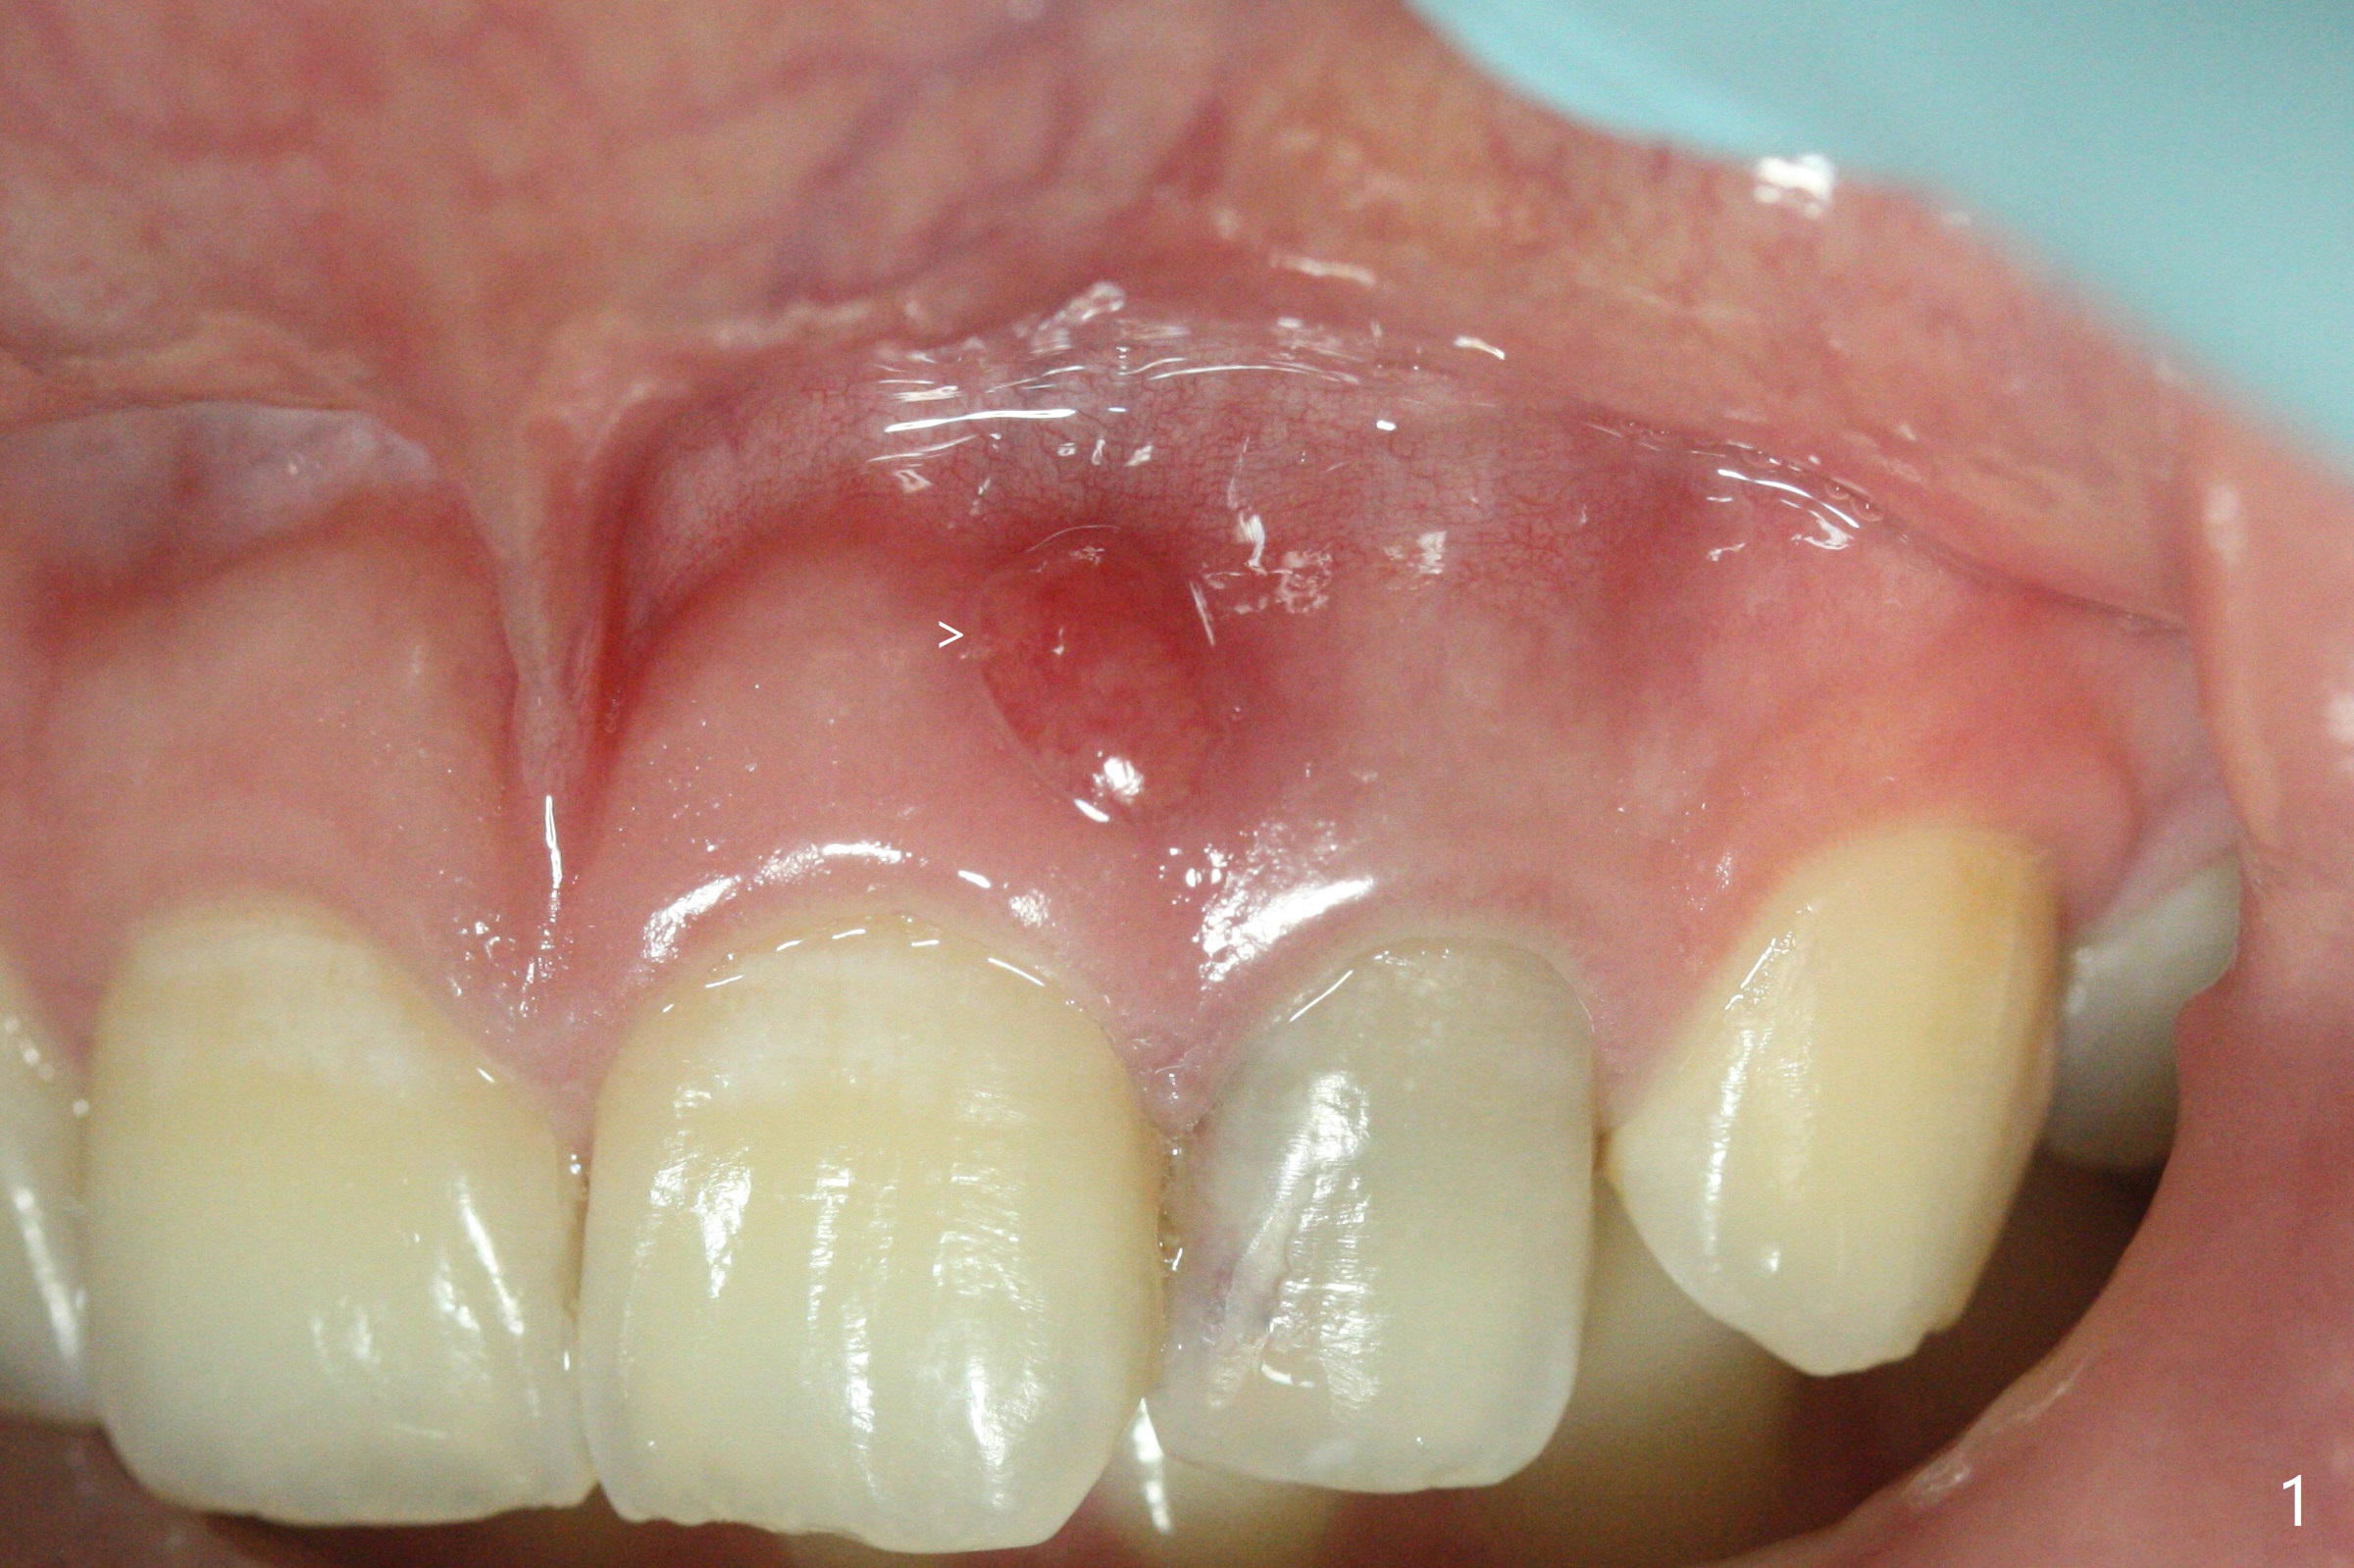

21岁女左上侧切牙根管治疗在别的诊所完成后出现瘘道(图一),近中阴影相当大(图二),应该如何处理?单独重做根管治疗足够吗?牙齿似乎没有松动,牙周袋正常,龋齿易感性高。牙列完整,仿佛没有咬合创伤迹象。可能由于经济问题,家长迟迟不带她去看专家。上个月我开始重做(图三:40/.04),能一次完成治疗吗?保险起见,放置氢氧化钙糊剂(图四)。一个月后病人回来,瘘道减小(图五),多次根管冲洗后,放置主牙胶尖(图六:40/.04),我当时在想根侧方阴影这么大,是不是有侧枝根管?如果扩根完善,根充时可能显示!是吗?其实这是最后根尖片(图七),40/.04主牙胶尖加三个fine, fine accessory gutta percha,并没有显示侧枝根管。